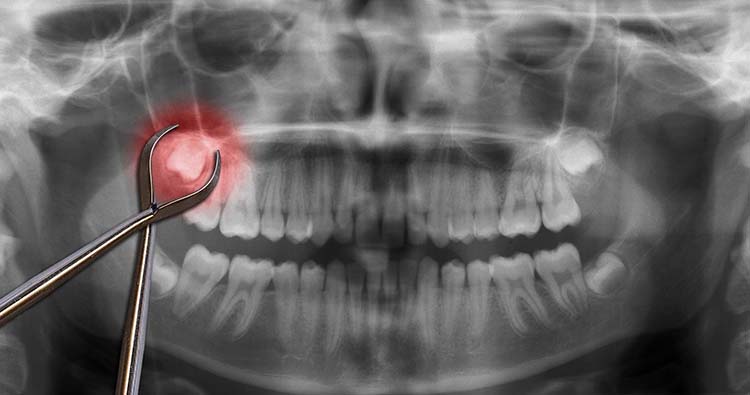

9. Growths Close to Your Wisdom Teeth

If your wisdom teeth are neglected, cysts, or sacs of fluid, may develop in your mouth. If left untreated, these cysts can seriously harm your jaw, teeth, and nerves.